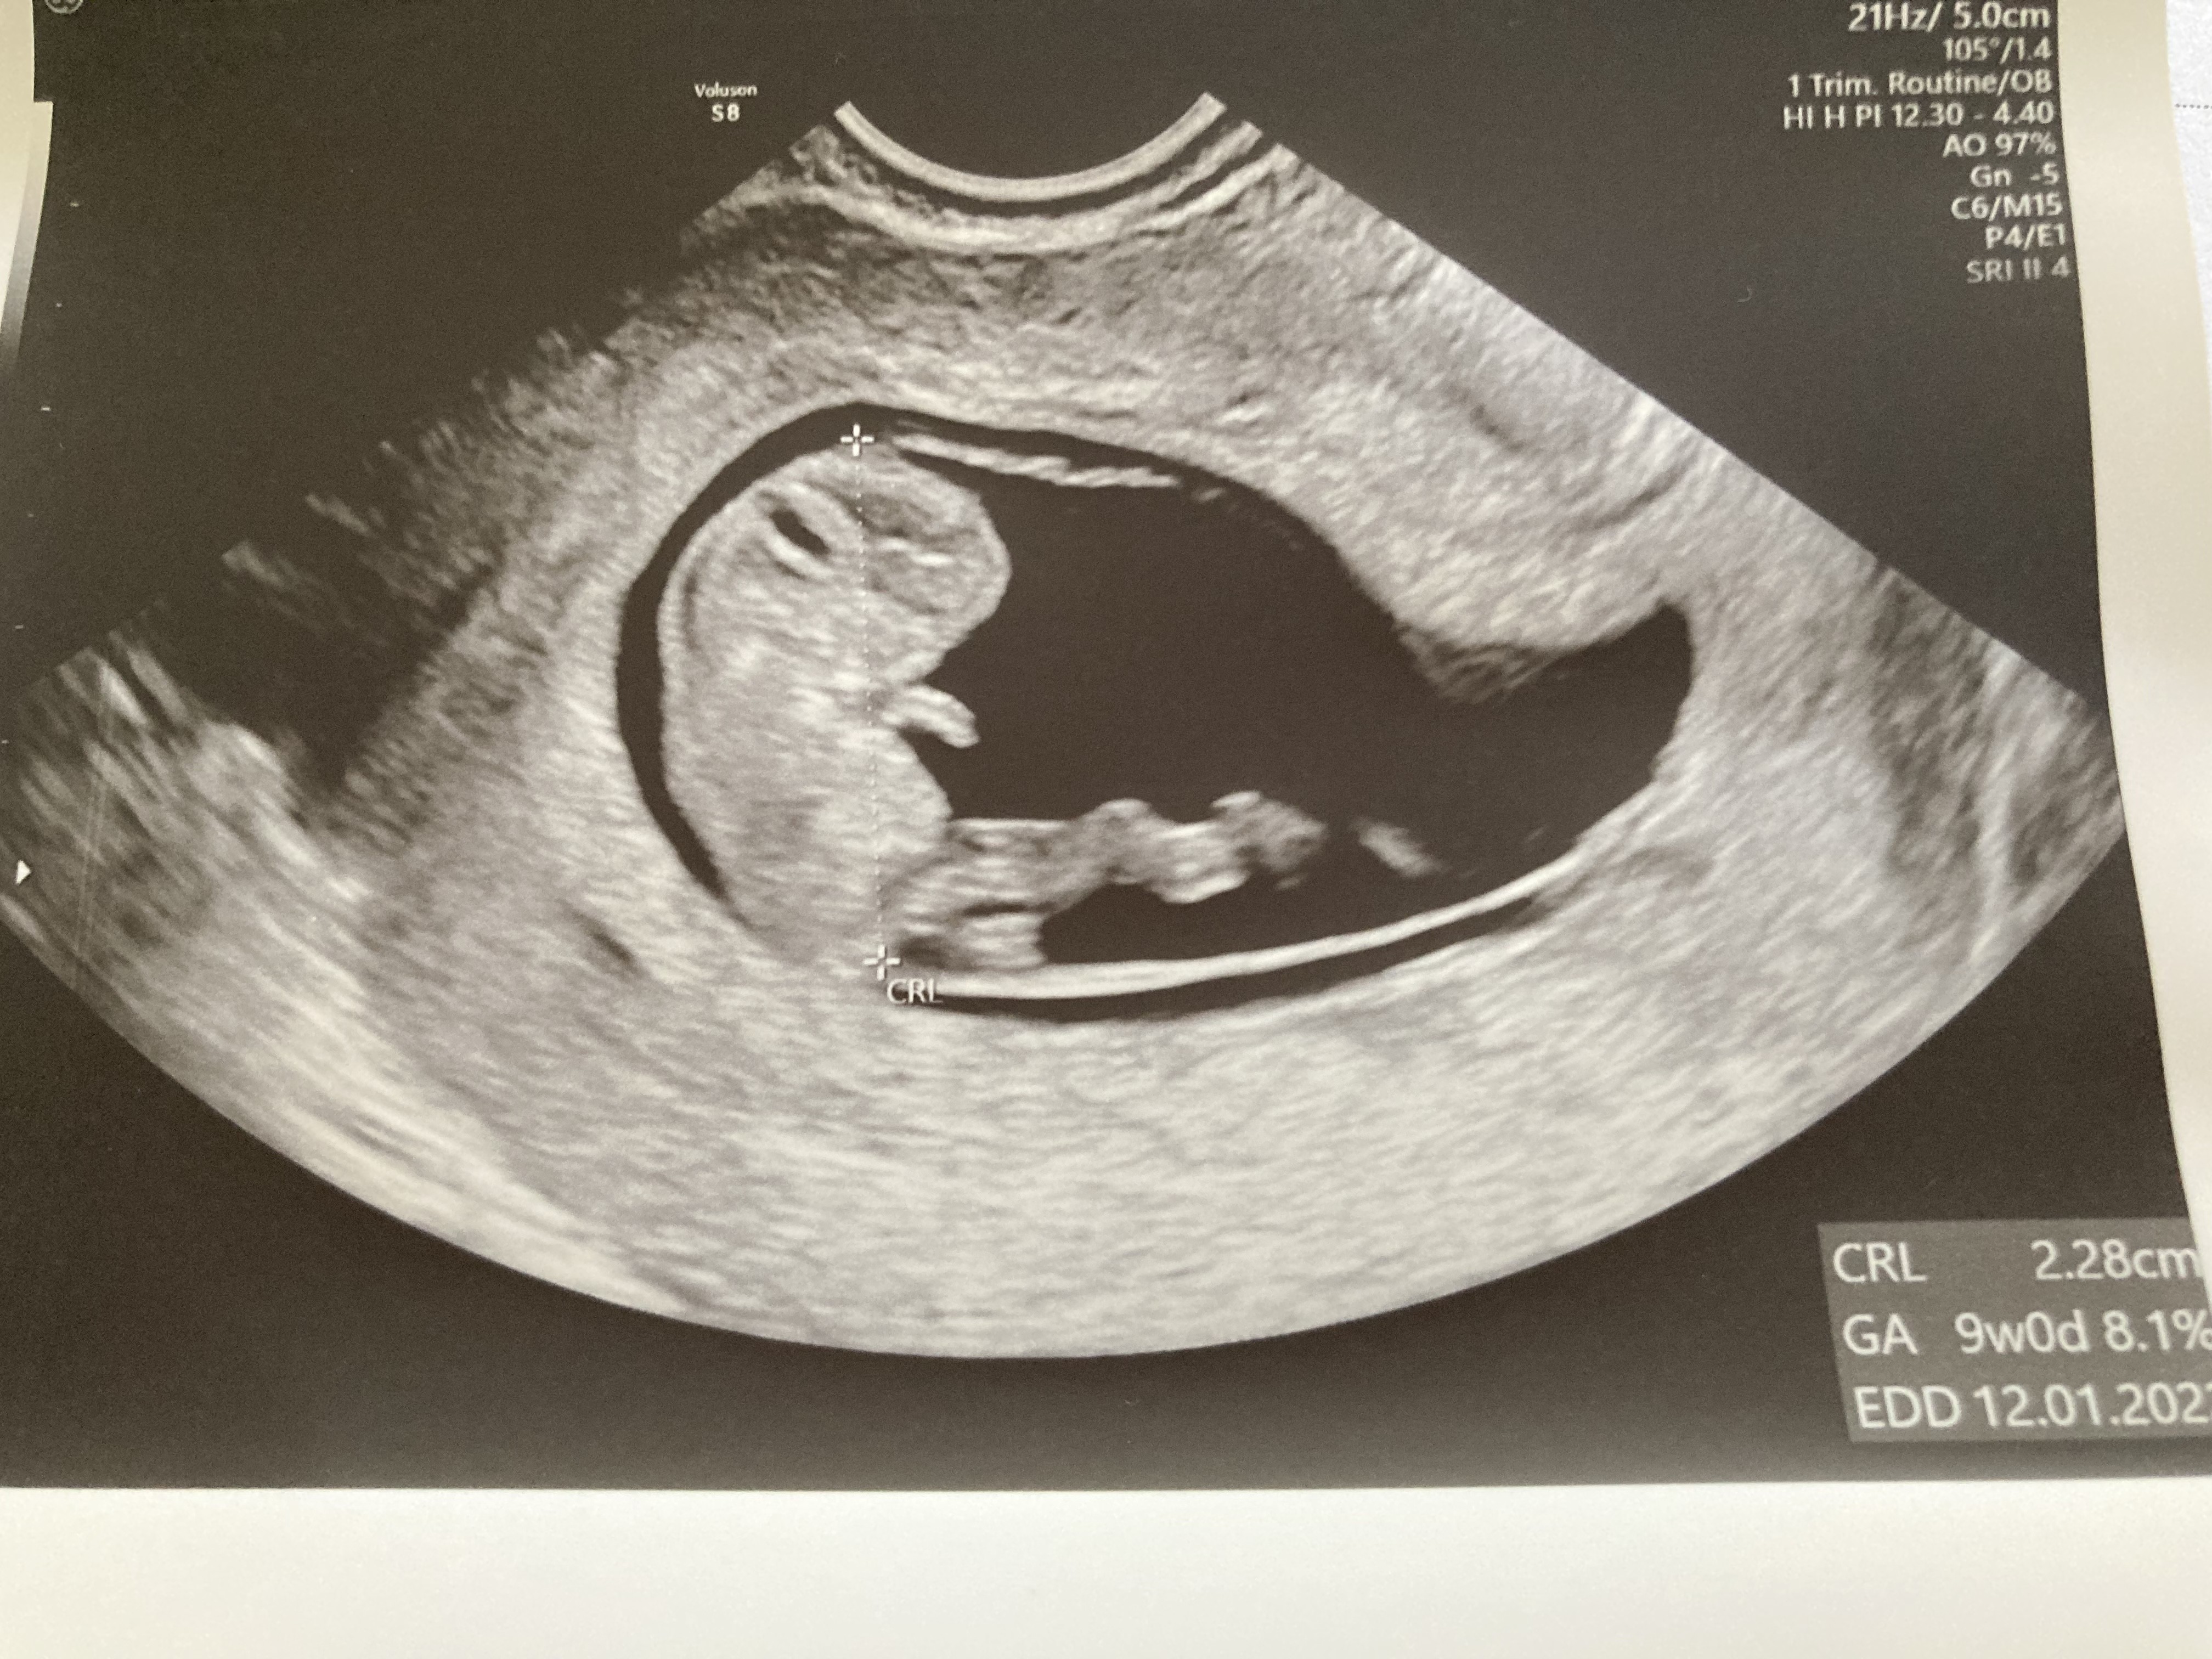

Wrzucam fotkę z usg, fasolka do Was macha